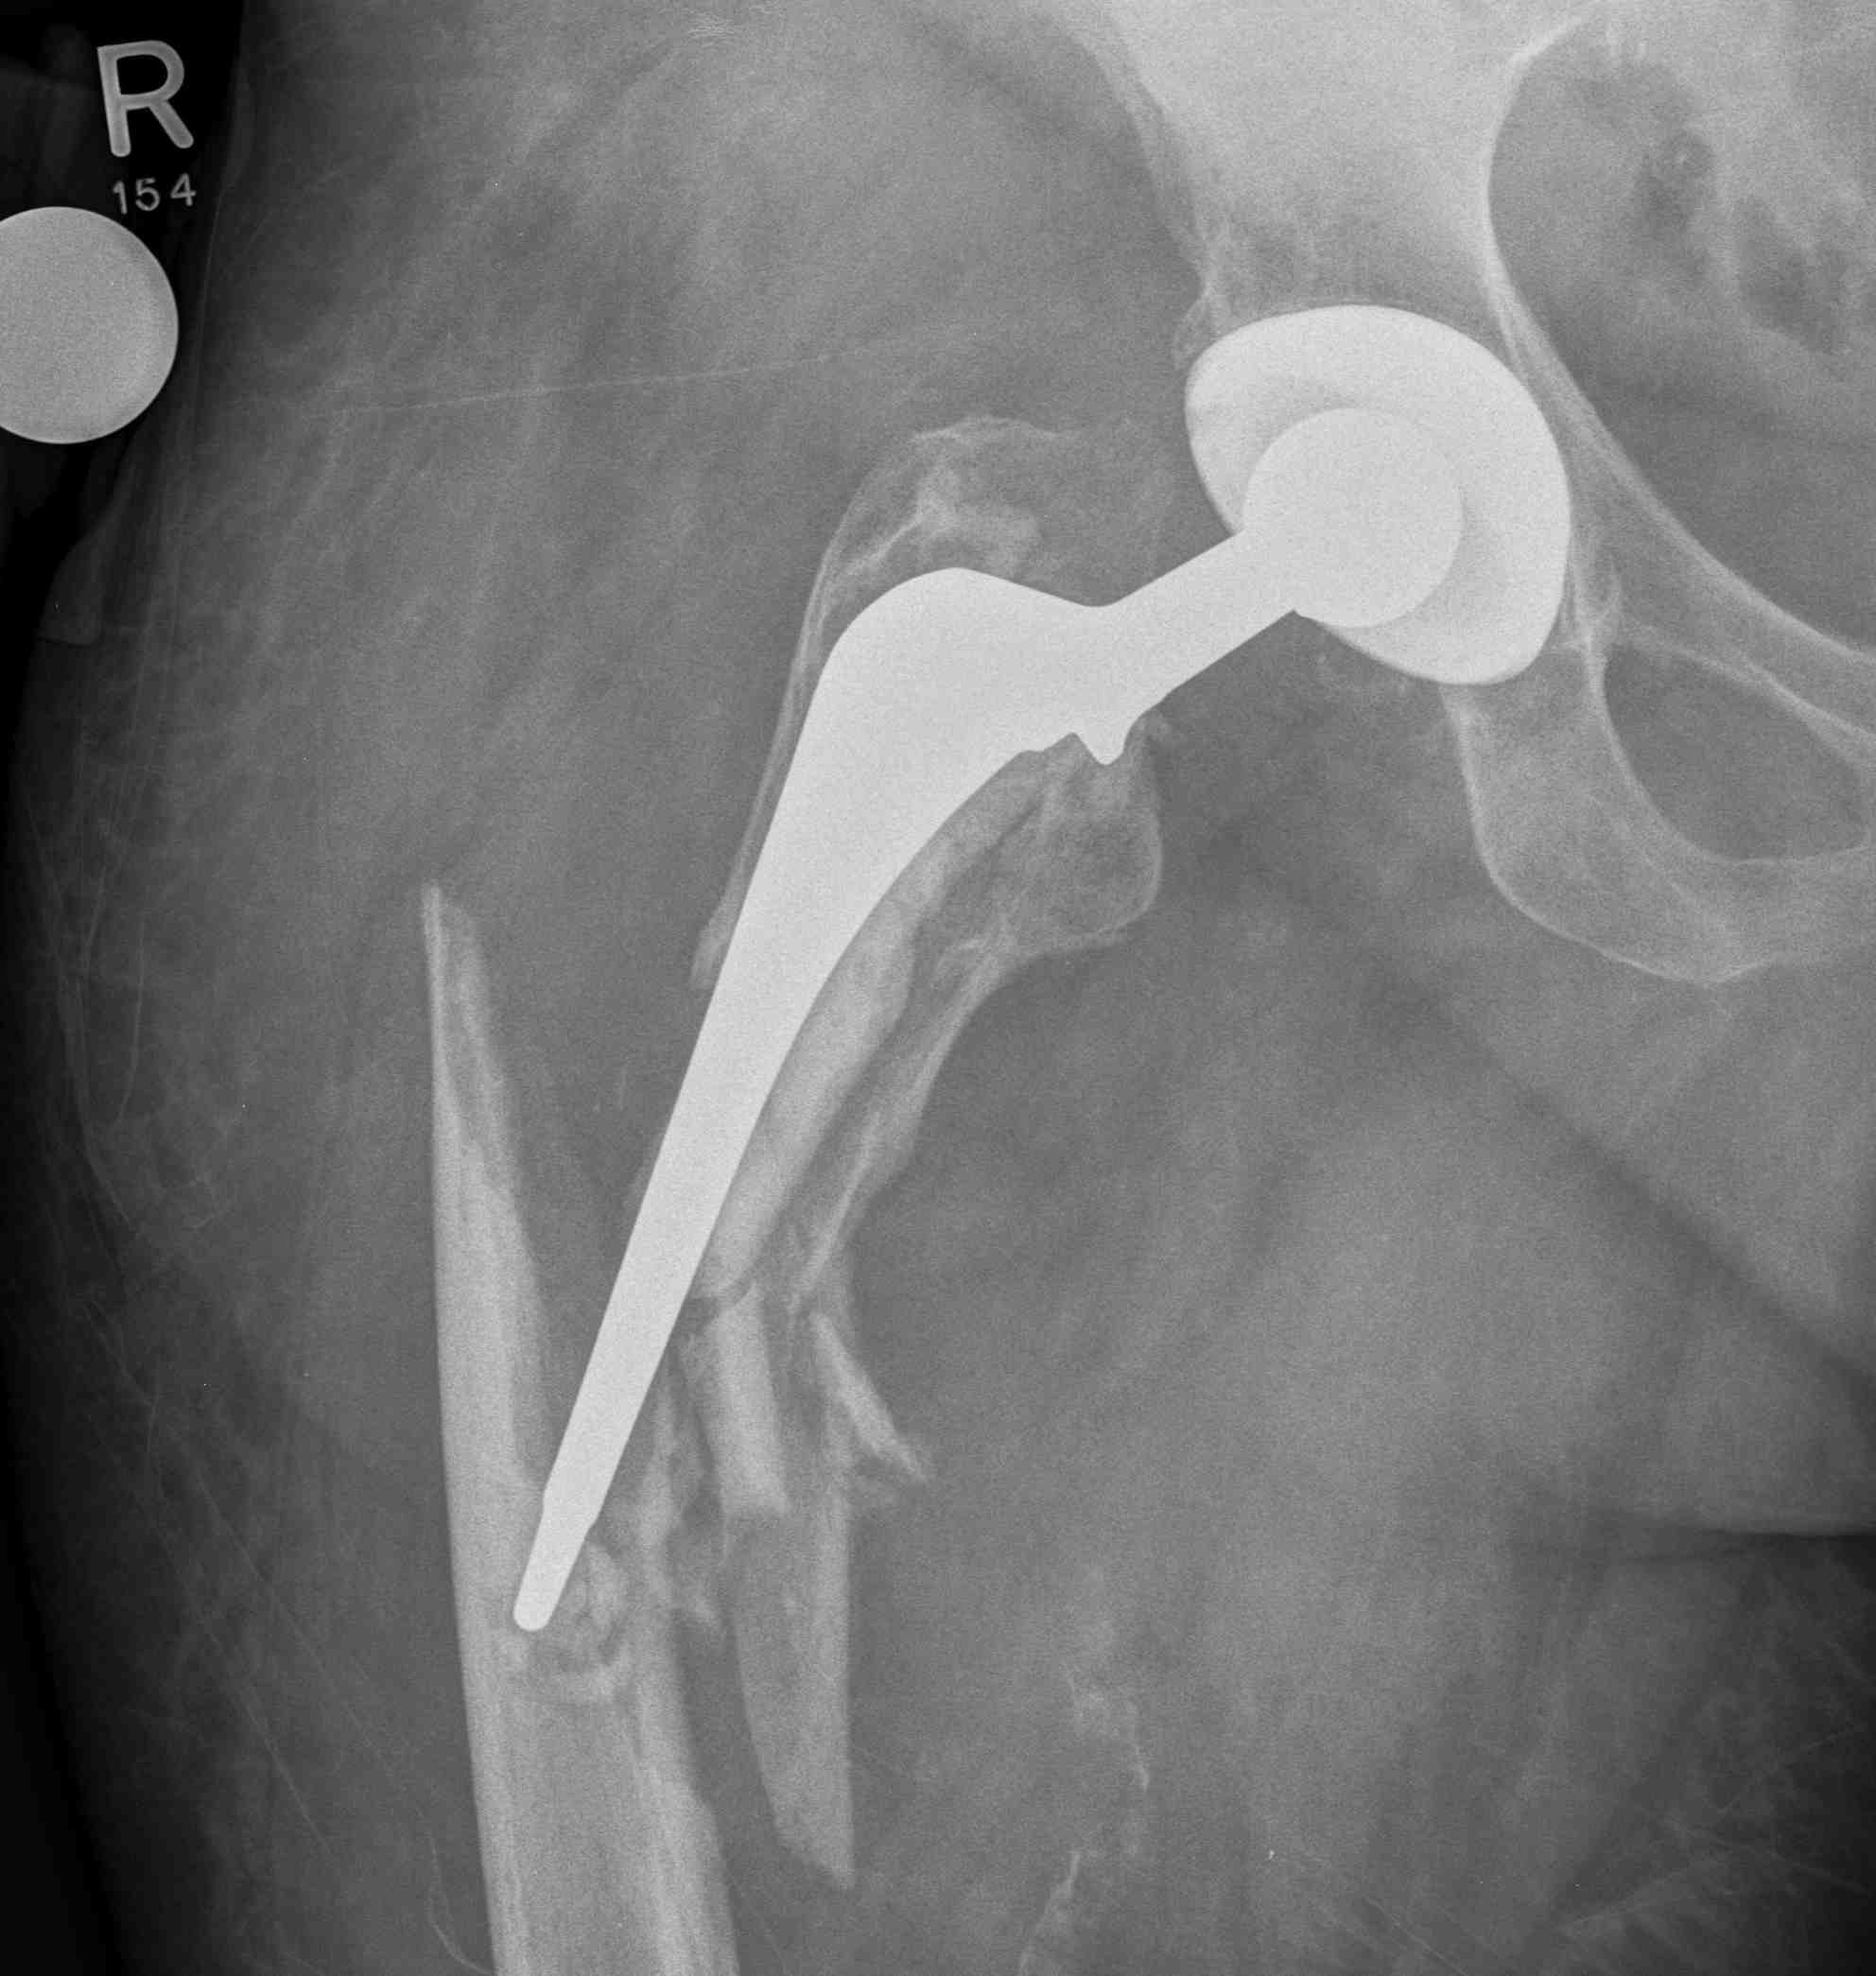

Long stem cemented revision